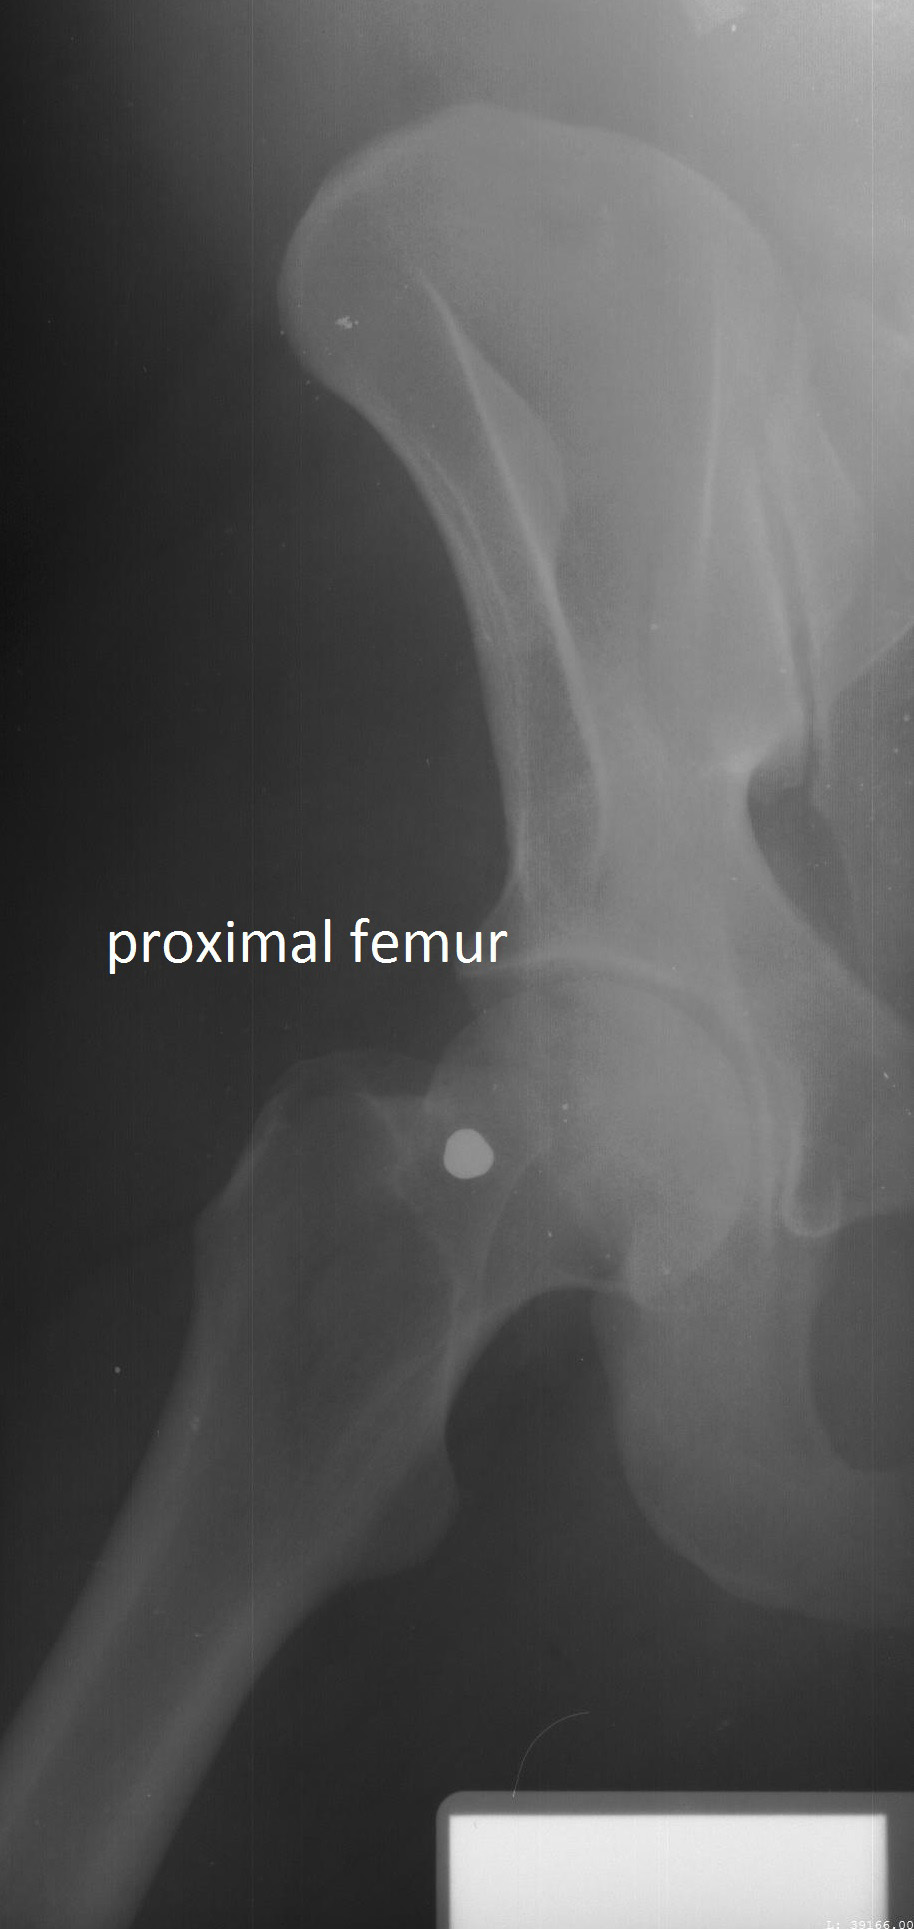

研究人员比较了20个人死前和死后的侧颅面(头骨的一侧)x光片,50个人的脊柱(脊柱)x光片,23个人的股骨近端(大腿)x光片。研究人员利用这些评估来为每个骨骼区域制定特定位置的标准。研究人员之所以关注这些骨骼区域,是因为它们是临床环境中x光照射最频繁的区域之一。

文摘:本研究的目的是评估在标准x线照片中可见的各种解剖特征的使用,并开发一套标准系统来评估一致性特征,以便通过x线照片比较作出积极的鉴别。研究中使用的x线片包括颅面(n = 41)、胸部(n = 100)和股骨近端(n = 49),这些x线片由北卡罗莱纳州首席法医办公室提供。根据一致性特征的数量对x线片进行评分,并使用分类决策树进行分析。分类树模型的准确性是利用接收者的工作特性来评估的。侧颅x线片需要两个或两个以上的一致性点,阳性鉴别的概率为97%。如果颈椎上存在一个以上的一致性特征,则有99%的概率正确识别。对于胸椎和腰椎,需要4个或更多的一致性特征才能有98%的正确识别概率。如果有1个或更多的股骨头和颈部一致性特征,正确识别的概率分别为94%和97%。本研究在3张标准的x线照片中确定了确认阳性识别所需的最小协调区域数目。